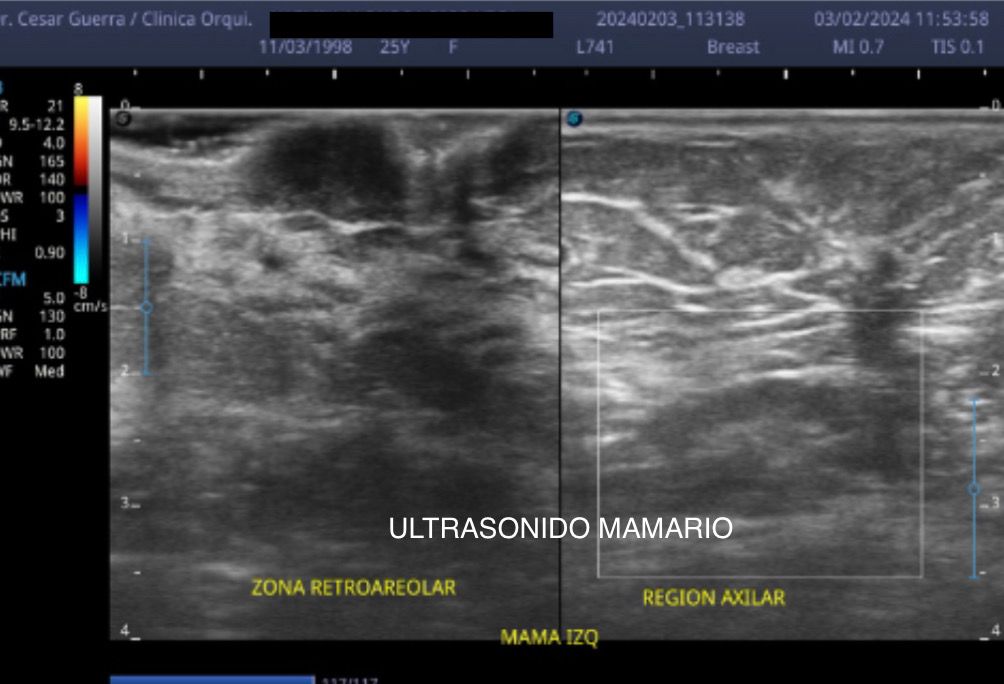

Médico general con 15 años de experiencia, master en enfermedades infecciosas y antibioticoterapia por parte de la Universidad Cardenal Herrera en Valencia, ademas de diversos diplomados en el área de Infectología y Parasitología, Urgencias, Imagenología y Medicina del Trabajo. He laborado en Hospitales y Clínicas en el área de Urgencias, en Laboratorios realizando estudios de Imagen, en especifico ultrasonidos de todo tipo desde básicos hasta avanzados incluidos los obstétricos estructurales, en Secretaría de Salud del Estado de Querétaro realizando ultrasonidos obstétricos para la detección de malformaciones en los tres trimestres del embarazo en diversos centros de salud, como médico de Empresas en el campo de Salud Laboral y actualmente en este consultorio en donde para su mejor atención y siempre buscando integrar la mayoría de las herramientas diagnosticas cuento con equipo de ultrasonido como apoyo en la exploración del paciente o como servicio diagnostico por imagen, realizo ultrasonidos convencionales (hepatobiliar (hígado, páncreas, vesícula y bazo), vías urinarias, ginecológico abdominal y transvaginal, tiroideo, prostático, testicular, pared abdominal) y especializados (dopler obstétrico en los 3 trimestres de embarazo), musculoesquelético en lesiones deportivas. También cuento con un equipo de electrocardiograma de 12 derivaciones para monitoreo completo del funcionamiento cardiaco, espirometria para evaluar la función pulmonar en la consulta, pruebas rápidas que se realizan en consultorio para detectar de forma mas precisa enfermedades infecciosas como Influenza A y B, covid19, infecciones urinarias, dengue, zika, chikungunya. Cuento con diversas vacunas para prevención de enfermedades. Siempre con el objetivo de dar el mejor servicio y atención a su salud. Lo espero en consulta para escucharlo y estudiar su caso de la forma más completa posible, estoy seguro de que tendremos las mejores opciones para su tratamiento. Mi tranquilidad es que usted se vaya con todas sus preguntas e inquietudes resueltas.

• Ultrasonido glándula mamaria

$800

Fui por un ultrasonido mamario y el Dr. César fue muy profesional. Explicaciones muy completas que nos hicieron sentir más tranquilos. Lo recomiendo ampliamente. Único detalle a mejorar fue la puntualidad.

• Consultorio privado Ultrasonido de mamario  •